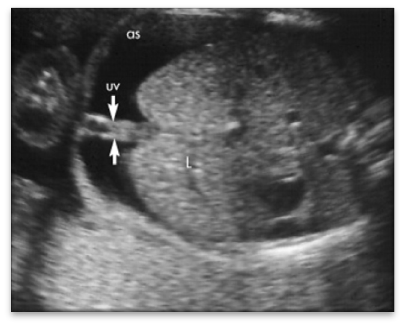

Urachal Dilation